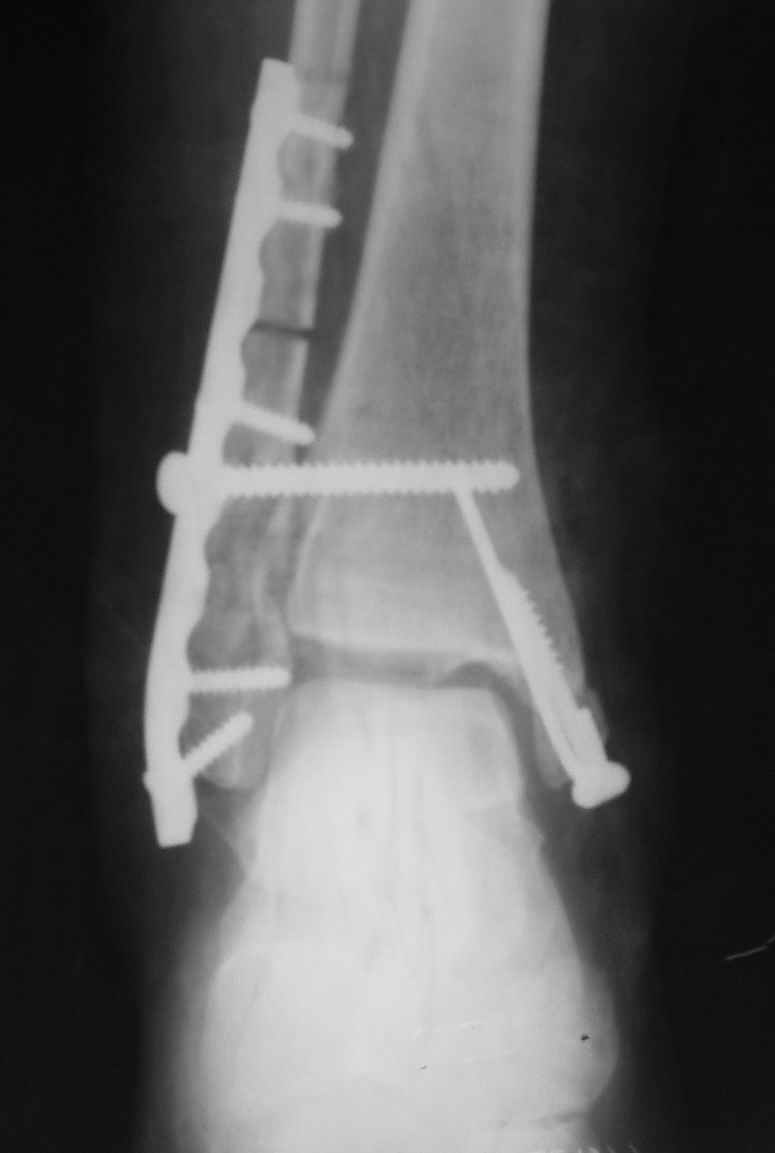

Уважаемые коллеги! Персонально, дорогой доктор Джолдас. Не знаю, почему почта к тебе не проходит - у меня почтовая программа "Bat", снимки в JPG. Выставляю через форум. 10 апреля я показывал снимки больной с застарелым переломо-вывихом голеностопного сустава. 9 июня прооперировал, снимки прилагаю. R-контроль через месяц ходьбы на костылях, все стоит также. Разрешил частичную (20кг) нагрузку на ногу, пока жалоб нет. Ход операции - сагиттальная остеотомия по линии неправильно сросшегося перелома малоберцовой кости, остеотомия с формированием внутренней лодыжки, попытка вправления подвывиха неудачна из-за того, что "не хватало" длины малоберцовой. Остеотомия малоберцовой кости выше синдесмоза. Остеосинтез.

На снимках хорошо сохранный голеностопный сустав, подвывих устранен, суставная щель одинаково прослеживается со всех сторон, небольшая нехватка длины малоберцовой и немного выступает пластина, а так в целом репозиция и фиксация удалось. Иногда, синдесмотический шуруп мы вводим немного длиннее, примерно на 3мм за медиальный кортекс, при переломе шурупа после нагрузки, шуруп легко удаляется с медиальной стороны. После 6 недель в гипсе можно разрешить нагрузку.